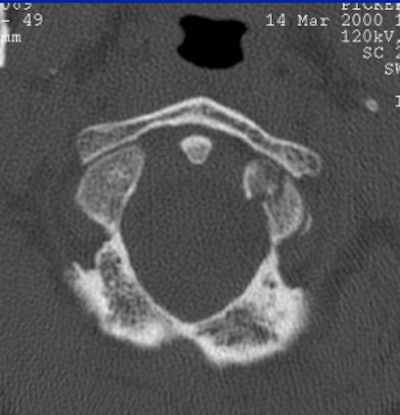

Whichever model is chosen, Cinnamon advised paying attention to the inverse relationship of contrast and spatial resolution, using the following case as an example (images F-G).

"On the 2.5-mm slice, you can see the occipital condyle fracture. If (you) go down to the 0.5-mm slice, you can see the fracture just as well -- maybe it looks a little sharper. But you can still identify the fracture on the thicker slice. The value for this is on the coronal and sagittal reformatted images from the 2.5-mm axials. There's a tremendous amount of stair-step artifacts. On the 0.5-mm images, you've eliminated the stair-step artifact because your spatial resolution is so good."

![]() |

| Image G |

The 0.5-mm slices offer fine bone detail, but pay a price on the soft-tissue images in terms of soft-tissue differentiation. Whereas the thicker (5-mm) slices fail to show the bone detail of the fracture well, but possess greater contrast resolution on the soft-tissue window to differentiate spinal cord from surrounding spinal fluid.